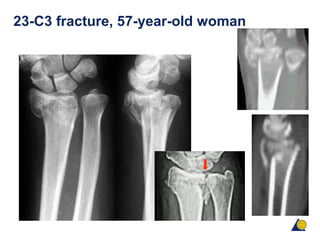

23-C3 fracture, 57-year-old woman

23-C3 fracture, 57-year-old female

โ€ข Direct visualization

โ€ข More irritation of the extensor tendons

โ€ข Risk of secondary tendon rupture